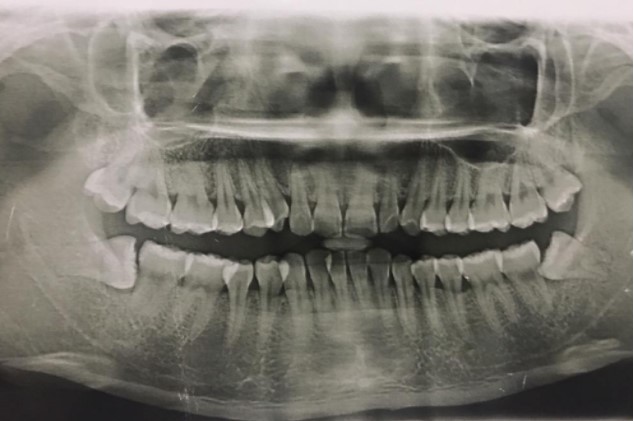

患者,男,38歲。上前牙變色1年,自述上前牙5年前受過外傷,唇側(cè)傾斜,檢查可見左上1牙冠變色,牙冠缺損近1/2,牙髓測試無反應,X線根尖片顯示患牙無明顯異常,全景片顯示雙側(cè)下頜智齒近中阻生,之前有發(fā)炎化膿病史,目前無咀嚼不適。口腔其余無異常。

檢查情況及X線片見下圖:

非主訴疾病的診斷依據(jù):X線全景片顯示雙側(cè)下頜智齒近中阻生。